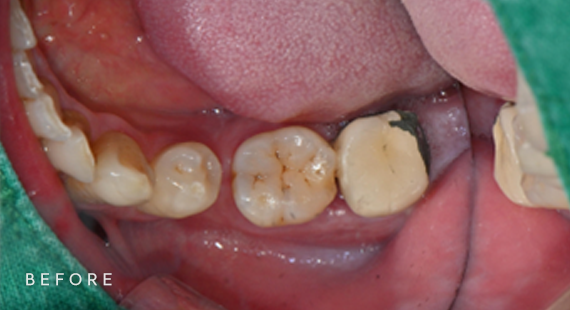

충치치료